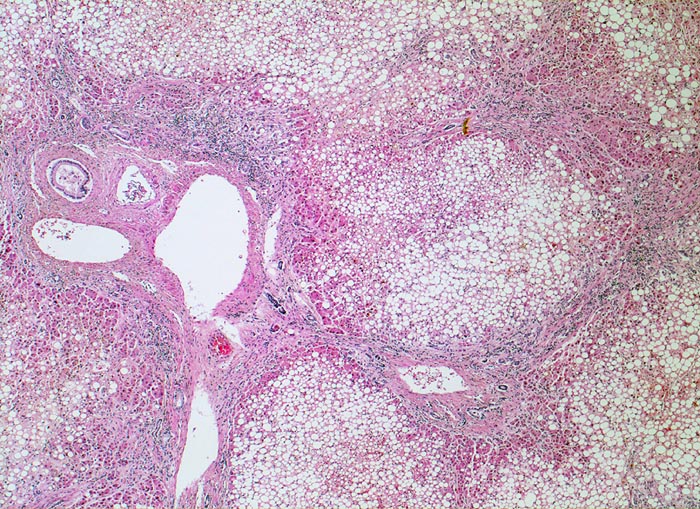

alkoholische Leberzirrhose, Steatose

Bindgewebebige Septen verbinden die Portalfelder und führen zur Ausbildung kleiner Knoten. Ca. 80% der Hepatozyten sind grobtropfig verfettet.

Die alkoholische Leberzirrhose ist bei fortgesetztem Alkoholabusus typischerweise feinknotig (Knotengrösse makroskopisch <3mm)